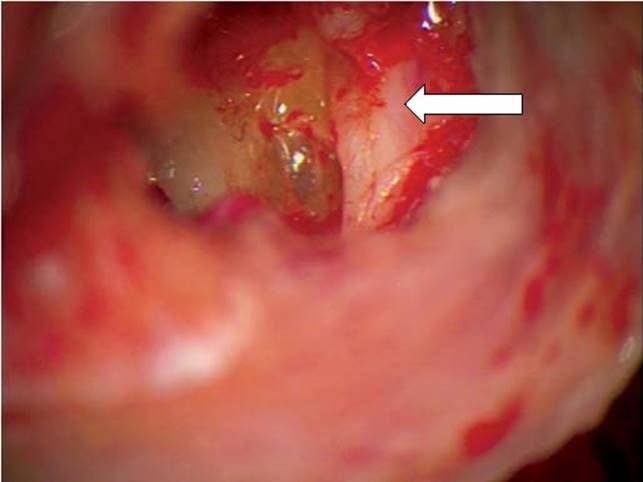

Facial paralysis can also be caused by chronic otitis media. In chronic otitis media, with or without associated cholesteatoma, direct inflammatory involvement or compression/invasion of the facial nerve is more likely than in cases of AOM (Fig. 5.2). More aggressive and earlier surgical intervention with mastoidectomy with possible facial nerve decompression may be needed. Chronic otitis media and/or cholesteatoma should be suspected and ruled out for any child with facial paralysis, particularly those who have a history of ear infections, hearing loss, or otorrhea. Medical therapy should include coverage for gram-negative organisms, including Pseudomonas aeruginosa, Proteusspecies, Klebsiella species, and Escherichia coli, and anaerobes such as Bacteroides, Peptococcus, and Peptostreptococcus that are more common in chronic ear disease.12

Figure 5.2 Facial nerve dehiscence in the left middle ear, with erosion of the bony fallopian canal just superior to the oval window. This 6-year-old child had cholesteatoma that eroded the stapes suprastructure as well as the fallopian canal, but did not have clinical evidence of facial nerve weakness. Arrow points to the tympanic facial nerve.